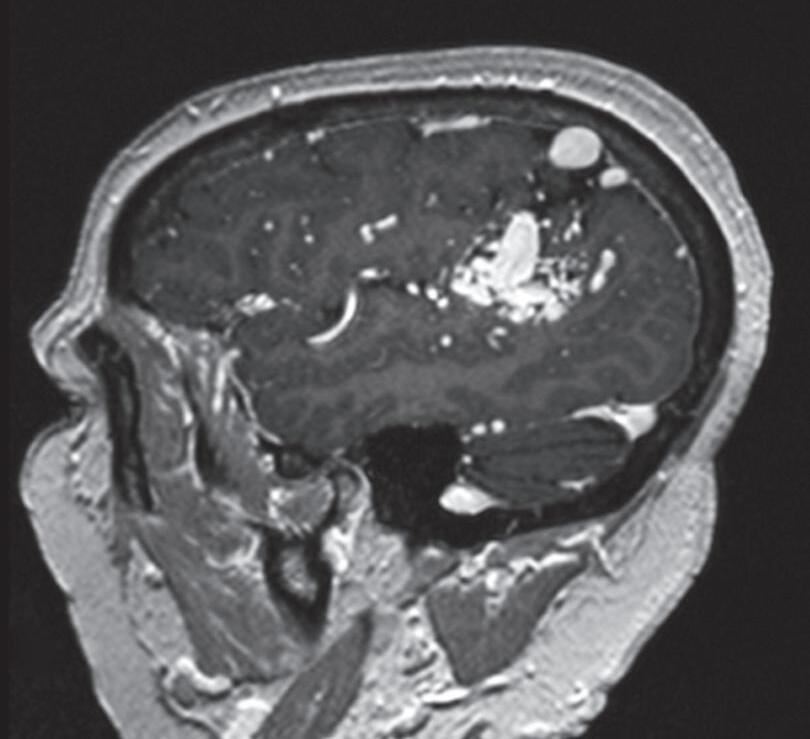

Fig. 1-15. RNM encéfalo T1 (a) sagital sem contraste e (b) axial com contraste demonstrando MAV grau 3, parcialmente embolizada, localizada no giro temporal superior e lobo parietal direito. (c) Arteriografia cerebral em perfil, demonstrando a irrigação pelos ramos da artéria cerebral média e posterior, com drenagem superficial nas veias de Labbé até o seio sigmoide, e o complexo de Trolard no seio sagital superior. O nidus da MAV está demonstrado pelas setas azuis grandes e a drenagem venosa pelas pontas de setas.